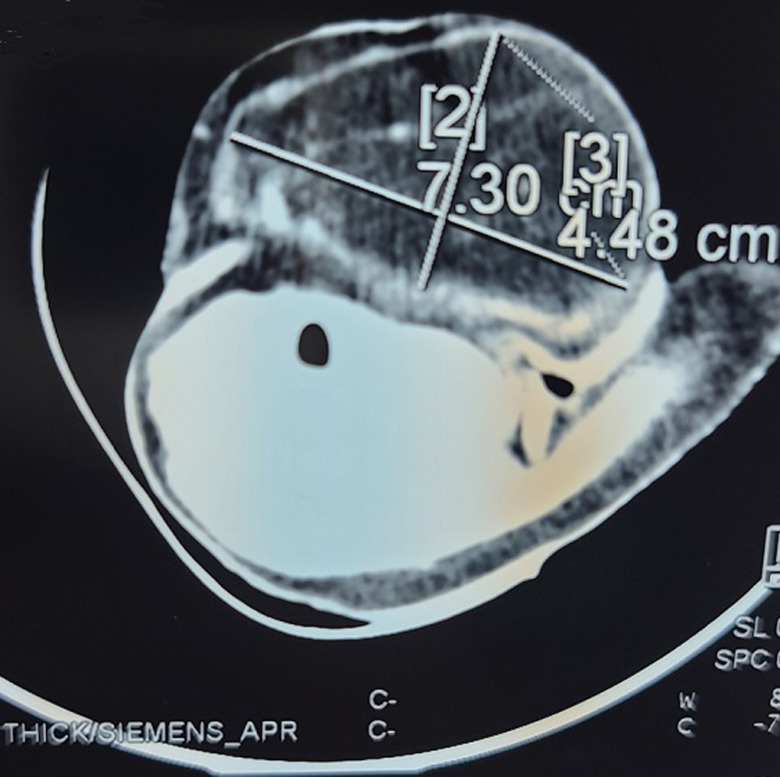

脂肪瘤是影响头颈部的间充质肿瘤,约占13%。然而,在儿科人群中很少有报道。我们在此报告一个6个月大的婴儿,没有明显的病史,入院治疗一个大的左侧颈椎肿块,已经进展了4个月。耳鼻喉检查发现左侧颈侧肿物,延伸至颏下区,长约7cm,无压迫迹象。宫颈CT显示脂肪密度肿块,符合脂肪瘤。患者行探查性宫颈切开术并切除肿块。组织学分析证实脂肪瘤的诊断。临床结果良好,随访15个月后无复发。虽然在儿童人群中罕见,宫颈脂肪瘤应考虑在婴儿宫颈肿胀。其临床表现与囊性淋巴管瘤相似。

Lipomas are mesenchymal neoplasms that affect the head and neck region in about 13% of cases. However, they are rarely reported in the pediatric population. We here report the case of a 6-month-old infant with no notable medical history, admitted for the management of a large left lateral cervical mass that had been progressing for 4 months. Ear, nose and throat (ENT) examination revealed a large left lateral cervical mass extending to the submental area, approximately 7cm in length, with no signs of compression. Cervical CT scan showed a fat-density mass, consistent with a lipoma. The patient underwent exploratory cervicotomy with excision of the mass. Histological analysis confirmed the diagnosis of lipoma. The clinical outcome was favorable, with no recurrence after 15 months of follow-up. Although rare in the pediatric population, cervical lipomas should be considered in infants with a cervical swelling. Its clinical manifestation is similar to that of a cystic lymphangioma.